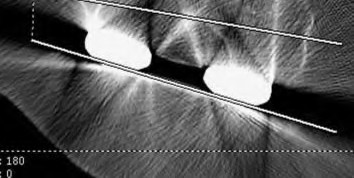

A 72-year-old female presents with progressive left thigh and knee pain for the last year. 5 years ago she sustained a femoral neck fracture treated with the implant seen in Figures A-C (current radiographs). The thigh pain is worse with weight-bearing. C-reactive

protein and erythrocyte sedimentation levels are within defined limits. Which of the following is the most likely cause of her pain?